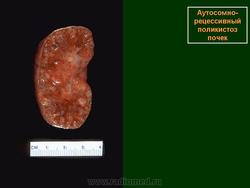

При аутосомно-рецессивной поликистозной болезни почек (АРПБП) отмечается симметричное поражение, при этом кистозные повреждения представлены образованиями размерами 1-2 мм, визуализация которых при ультразвуковом исследовании плода не представляется возможной. Эхографическими критериями заболевания являются: выраженная двусторонняя нефромегалия («большие белые почки»), отсутствие эхотени мочевого пузыря и маловодие. Увеличение размеров почек иногда бывает настолько значительным, что они занимают большую часть поперечного сечения живота плода.

ID: 12922 Autosomal recessive polycystic kidney disease (ARPKD) Dr Frank Gaillard - 3 Feb 2011 Autopsy specimen from an infant with autosomal recessive polycystic kidn...